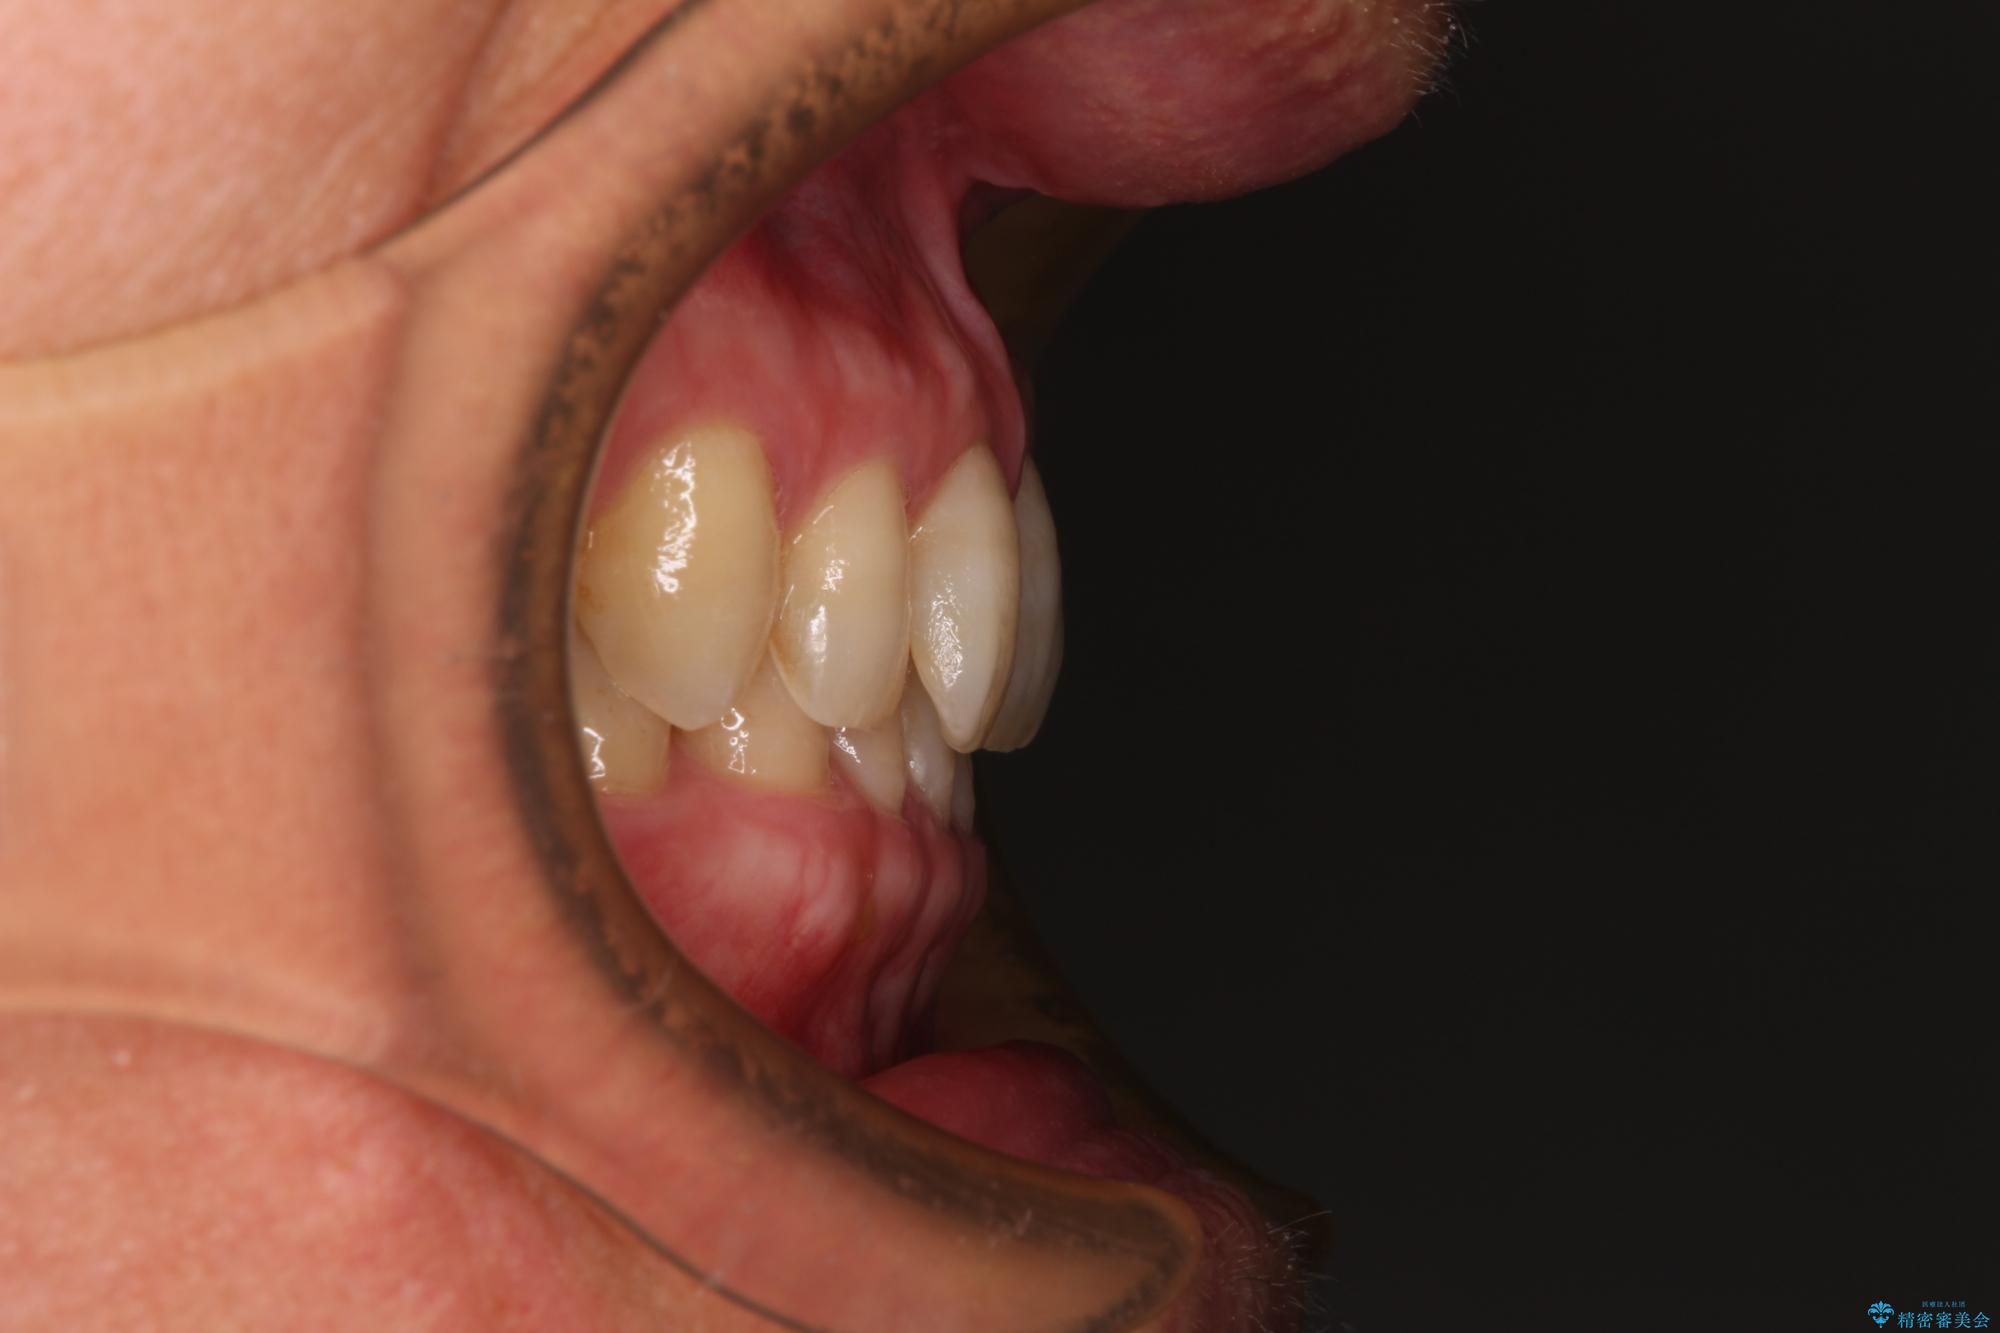

ディープバイトが改善され、睡眠時の食いしばりも緩和され、顎への負担が軽減されました。